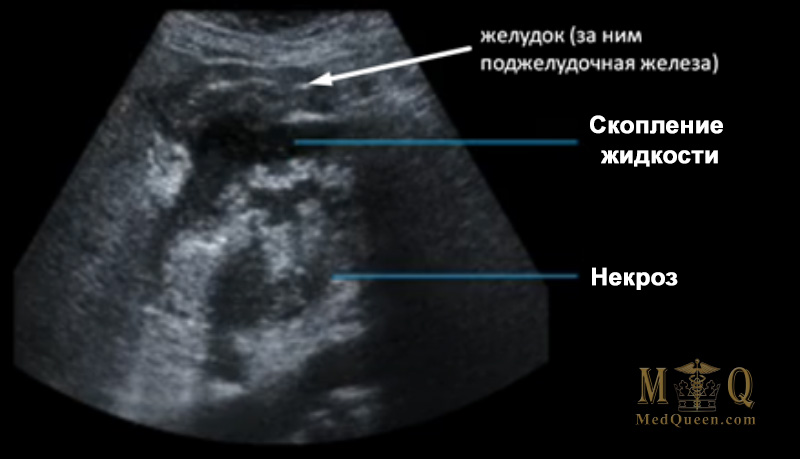

Некротический панкреатит